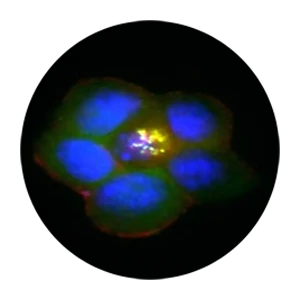

Metabolism and innate immunity through the lens of lipids and membranes.

At the IGBMC in Strasbourg, the Ricci Lab explores how membranes and organelles orchestrate inflammation and metabolic control. By examining inflammasome assembly in macrophages, neuroendocrine regulation in the hypothalamus, and insulin secretion in beta cells, we aim to uncover shared principles of membrane and organelle function in health and disease. Our mission is to translate these insights into novel strategies against chronic inflammatory and metabolic diseases.